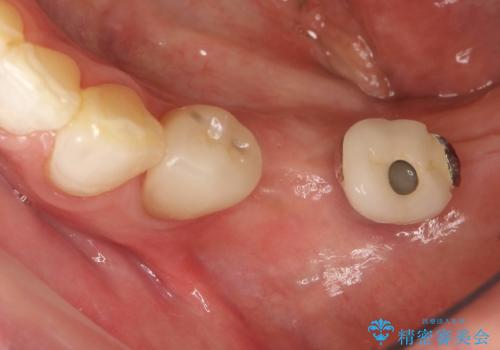

奥歯がない インプラント治療でかみあわせを回復

- 単独のインプラント補綴にて咬合の回復を計画した。

インプラントの種類:straumann SLActive

かぶせ物の種類:Bellezza screw retain